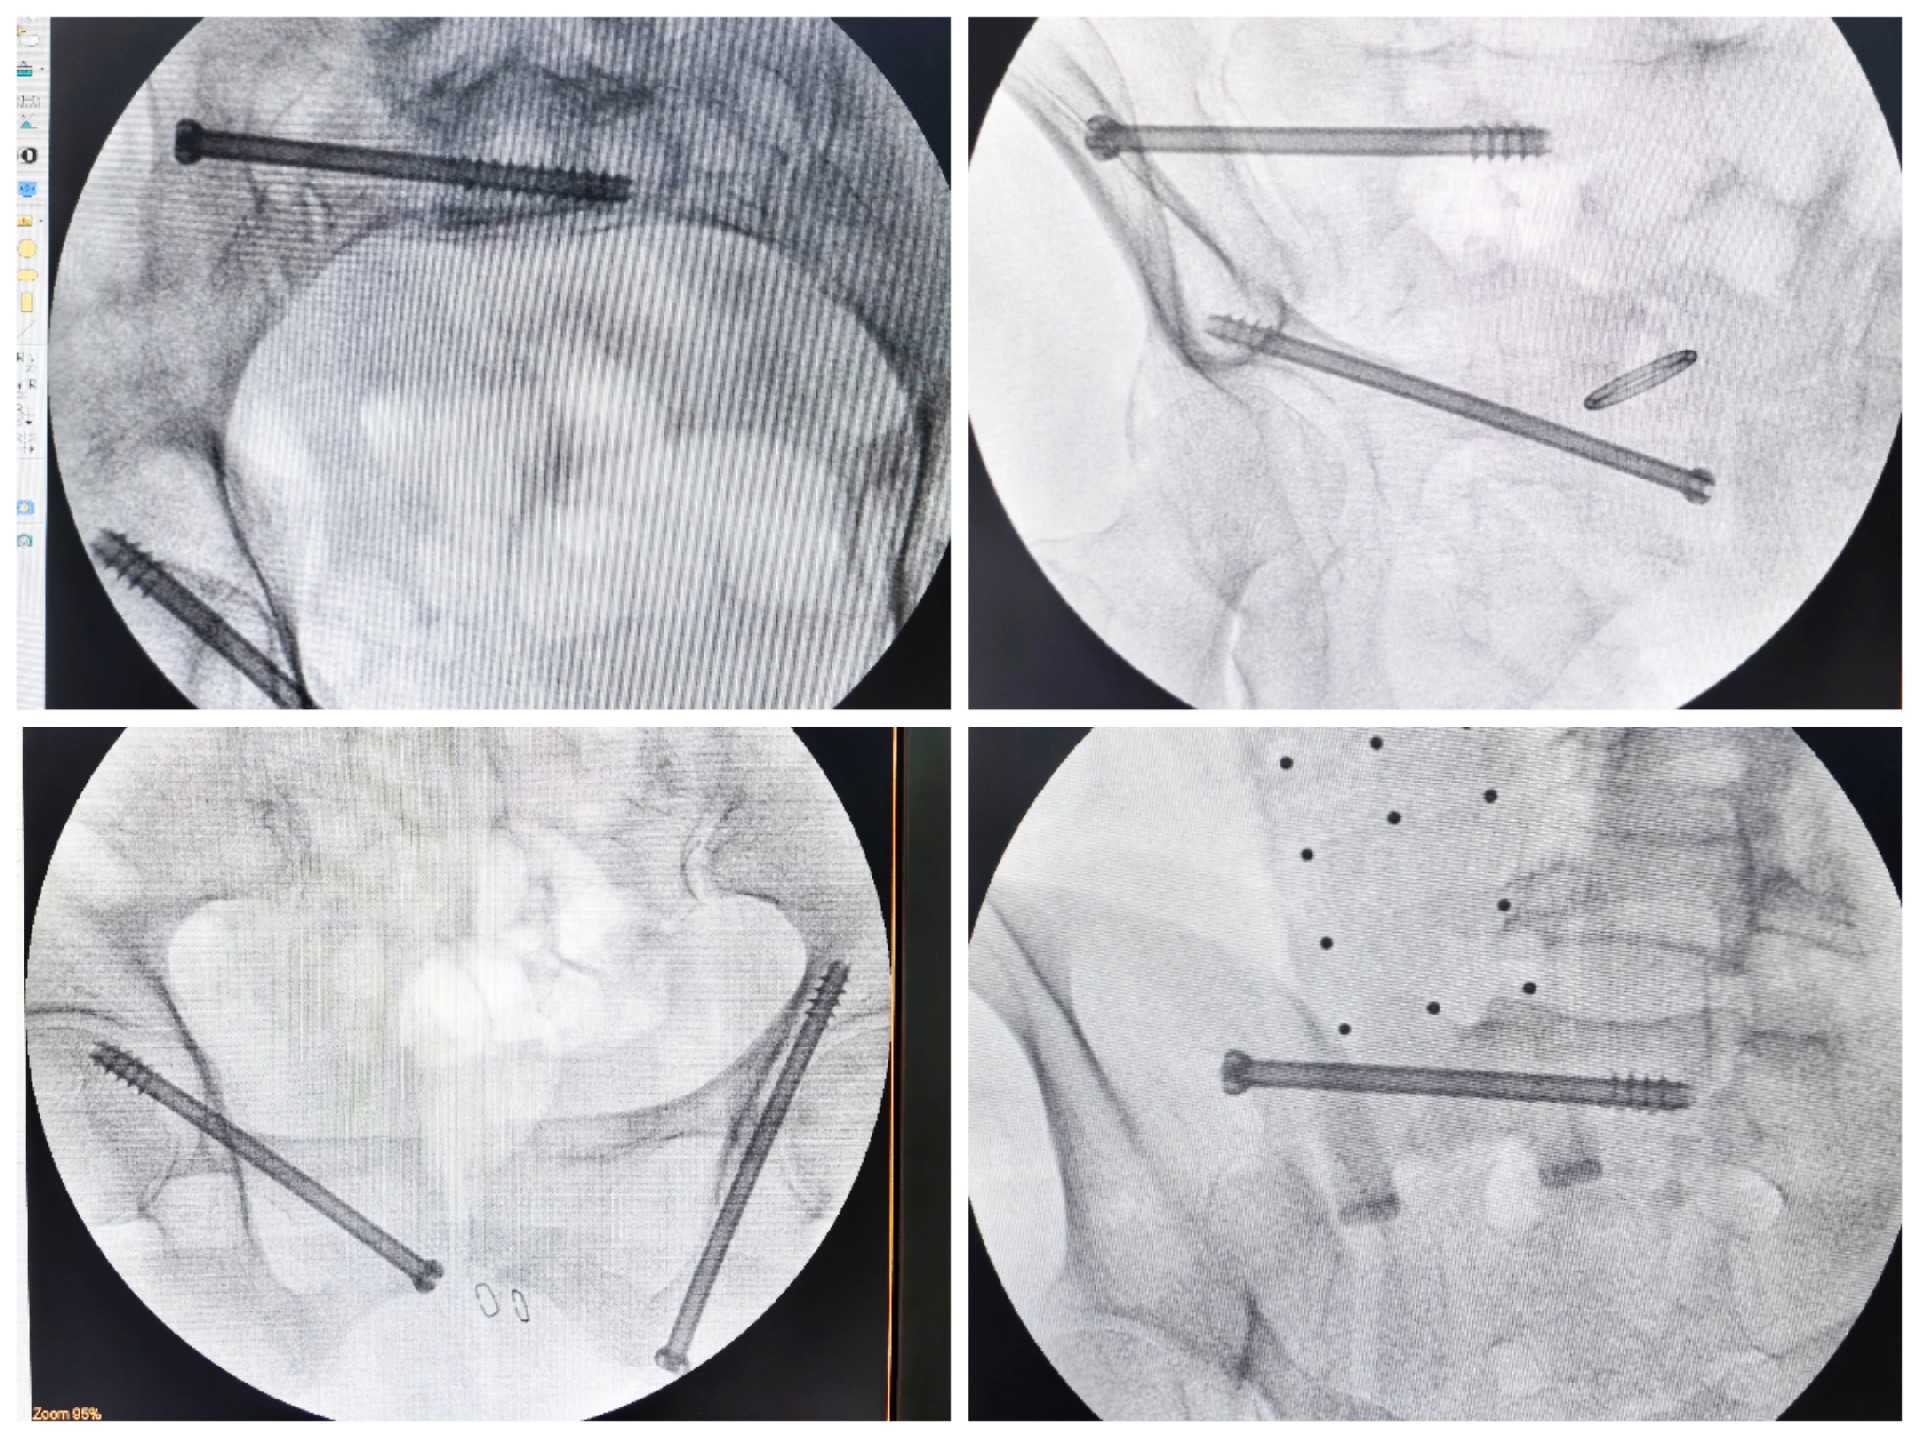

傳統(tǒng)的骨盆骨折微創(chuàng)手術(shù)中,骶髂螺釘?shù)嚷葆斨萌氲碾y點在于骨盆部位解剖十分復(fù)雜,螺釘置入如有偏差極易損傷重要神經(jīng)及血管,手術(shù)不僅依靠手術(shù)醫(yī)師豐富的經(jīng)驗,還需要術(shù)中反復(fù)的C型臂透視及調(diào)整,對患者及醫(yī)生都有較大輻射。而利用HoloSight知見創(chuàng)傷骨科機器人進行骨盆骨折微創(chuàng)手術(shù),通過高精度光學(xué)定位追蹤技術(shù)與混合現(xiàn)實技術(shù),使整個微創(chuàng)手術(shù)全程可視化,可以在電腦屏幕上實時顯示螺釘?shù)木珳?zhǔn)置入位置,降低手術(shù)風(fēng)險,提高手術(shù)效率及安全性。

術(shù)前,手術(shù)團隊認(rèn)真分析討論病例,全面掌握骨盆骨折微創(chuàng)治療的關(guān)鍵技術(shù),提前設(shè)計手術(shù)方案并反復(fù)模擬演練手術(shù)過程。術(shù)中,利用HoloSight知見創(chuàng)傷骨科機器人規(guī)劃骨折復(fù)位方案及定位螺釘通道,實現(xiàn)精準(zhǔn)微創(chuàng)手術(shù)。手術(shù)通過不足1cm小切口完成,最大程度地減少了術(shù)中出血,術(shù)中幾乎都是一次性成功精準(zhǔn)微創(chuàng)地置入內(nèi)固定螺釘,減少了醫(yī)源性操作對骨折周圍骨質(zhì)的影響,實現(xiàn)骨折微創(chuàng)固定的同時盡可能提高骨折固定的穩(wěn)定性,為術(shù)后患者的快速康復(fù)創(chuàng)造了有利條件。